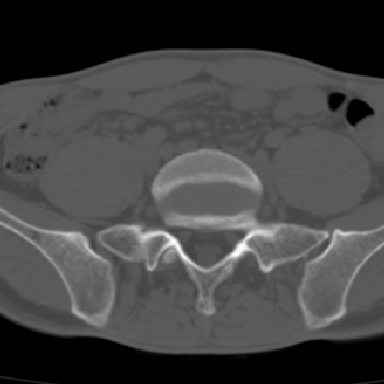

m 30 腰背部不适半年; 清晨时僵硬; 活动症状有所改善

双侧骶髂关节下2/3关节面模糊,毛糙,可见小囊状骨质破坏区.支持强直性脊柱炎.

强直性脊柱炎的早期改变!不仅表现为双侧骶髂关节,第5腰椎与骶椎间的关节突关节也有类似改变。

双侧骶髂关节下2/3关节面模糊,毛糙,髂骨侧可见小囊状骨质破坏区,骶髂关节间隙增宽(软骨破坏期)。支持早期强直性脊柱炎。

双侧骶髂关节下2/3关节面模糊、毛糙,可见小囊状骨质破坏区,呈虫咬状改变,周围可见增生硬化.支持强直性脊柱炎早期表现.

双侧骶髂关节髂骨面硬化,毛糙,小囊变,属于早期强直性脊柱炎